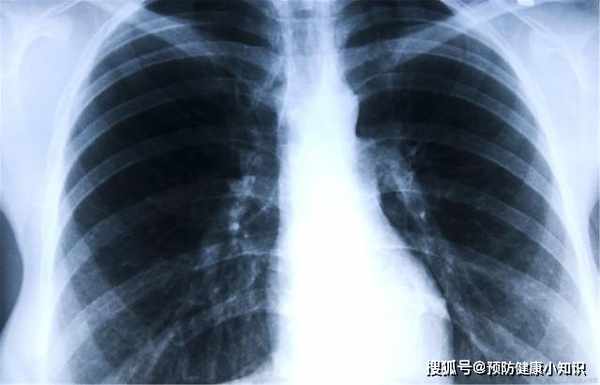

儘管鄭琪心存懷疑,認為自己也沒有咳嗽,身體也不疼不癢的東西,為什麼要做肺CT呢?但老同學的話她還是聽進去了,誰知道做CT後才發現,有一個拳頭大小的腫塊在肺,結果被診斷為肺癌晚期。

想要早發現,早治療肺癌,CT不可少

想要早期發現疾病,最好的方法是去醫院檢查和治療,這取決於老百姓的好習慣,定期體檢,最好做CT檢查,尤其是30歲以上的年齡,應該每年肺癌篩查、胸部CT。想